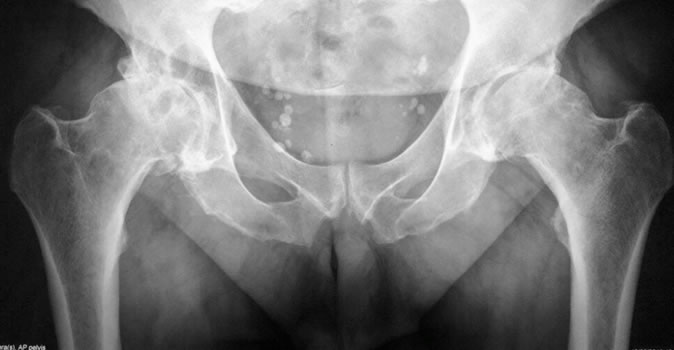

Existen numerosas indicaciones para el reemplazo articular, principalmente la artrosis de cadera. Se define artrosis a la pérdida del cartílago articular.

El diagnóstico principalmente está basado en el examen físico. El dolor inguinal con irradiación hacia el muslo y la limitación de la movilidad articular son los hallazgos más frecuentes en el consultorio.

Los estudios por imágenes son complementarios a la revisación médica. Las radiografías comparativas de ambas caderas, y eventualmente una tomografía computada o resonancia magnética nuclear, nos permiten analizar la articulación con los datos obtenidos en la revisación, así como también la planificación adecuada para un eventual procedimiento